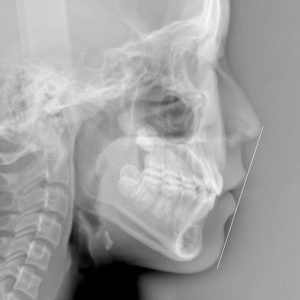

新着情報 336 治療後セファロ側面 – コピー Tweet 投稿日 : 2022年07月18日(月)カテゴリー : コメントを残す コメントをキャンセルメールアドレスが公開されることはありません。 * が付いている欄は必須項目ですコメント 名前 * メール * サイト 12歳 女性「”八重歯”を 治して欲しい」15か月(上下顎叢生) ≫